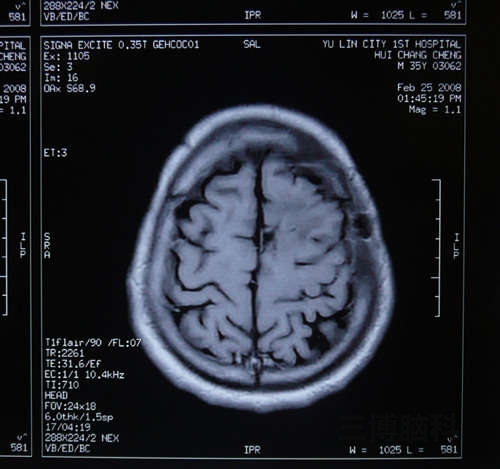

小脑蚓部占位性病变(囊肿)切除术案例

患者赵某某,40岁,男性,北京人,于2014年2月13日以阵发性头晕头痛3月,加重伴呕吐1周入院。 现病史: 患者于3月前2017-06-01

脑囊肿头痛病案

患者某某,男34岁,今年5月份开始头痛,一直很频繁,主要是右侧后部,剧烈疼痛,胀痛,已经严重影响工作和其他2017-06-01